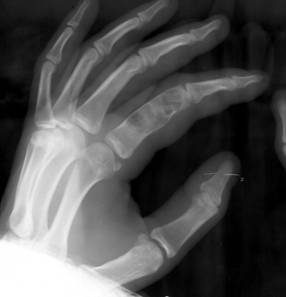

Fig. 80 – Encondrom falanga proximala index

b)   Condromul – afecteaza preferential metacarpienele si falangele, au evolutie lenta si sunt descoperite fortuit. In raport cu directia de dezvoltare fata de canalul medular, se descriu: encondroame, care iau nastere in metafiza si se dezvolta spre canalul medular si eccondroame care au dezvoltare predilecta spre corticala osoasa, aparand ca niste lacune nestructurate, neomogene prin prezenta de calcificari, bine delimitate de osul sanatos, impingand si subtiind corticala.